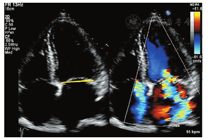

Ⅰ型:瓣叶活动正常而瓣膜功能失调(图2)。在Ⅰ型功能失调中,收缩期和舒张期瓣叶活动幅度正常,反流的原因为瓣叶穿孔或瓣叶对合不良导致(瓣环扩张)。

Ⅱ型:瓣叶活动过度的瓣膜功能失调(瓣膜脱垂)(图3)。定义为一个或多个瓣叶活动度增加,瓣叶的游离缘在瓣叶关闭时超过了瓣膜口关闭时的平面,血流动力学结果提示为瓣膜反流,由于腱索断裂或延长,或者乳头肌断裂导致。

Ⅲ型:瓣叶活动受限的瓣膜功能异常(图4)。在Ⅲ型功能失调中,Ⅲa类指一个或多个瓣膜的运动在瓣叶开放或关闭时受到限制导致不同程度的狭窄或反流(瓣膜及瓣下组织增厚或钙化);Ⅲb类指一个或多个瓣叶的运动在瓣叶关闭时受到限制导致的反流(此类病变多为缺血性导致)。